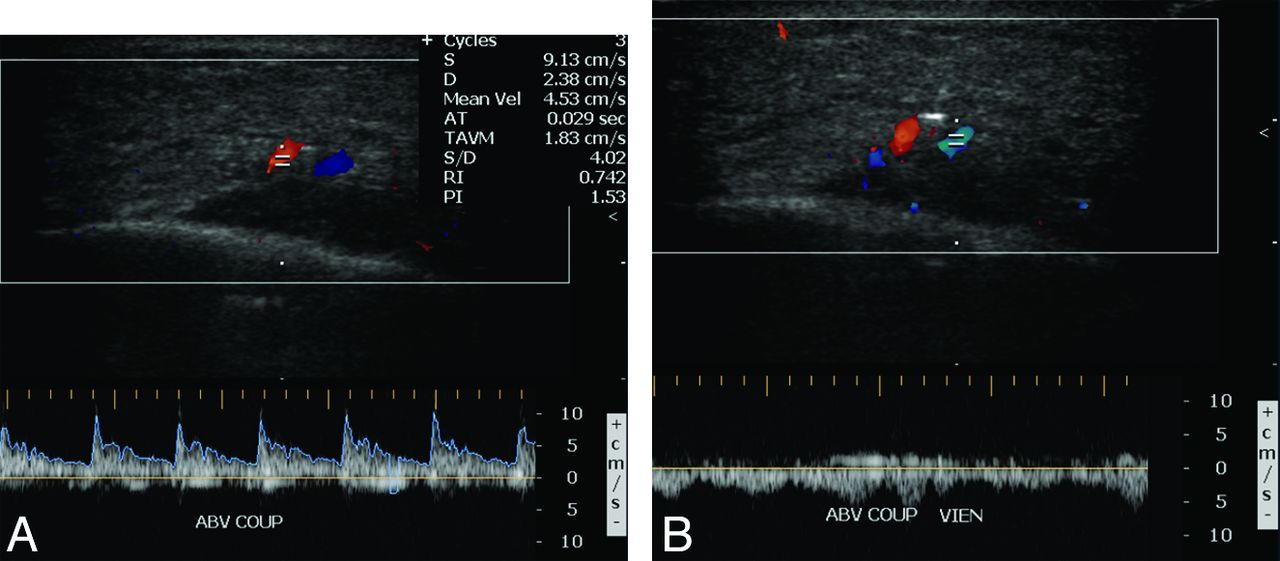

Free gracilis transfer is an effective method of smile rehabilitation for facial paralysis in selected patients (Fig 7).11⇓⇓–14 The gracilis muscle is harvested from the thigh with its neurovascular supply (Fig 8). The graft is then inset in the plane deep to the superficial musculoaponeurotic system and extends from the zygomatic arch to the modiolus of the oral commissure (Fig 9). The vascular pedicle of the graft is typically anastomosed to the facial artery and vein, and the obturator nerve can be anastomosed to a cross–face nerve graft and/or the masseteric branch of the trigeminal nerve.15,16 Vascular ring coupler devices are often used for the venous anastomosis.17 Depending on the particular type, the ring coupler may appear as a hyperattenuated circular structure overlying the angle of the mandible (Fig 10). Postoperative flap monitoring by physical examination alone is challenging and is often supplemented with use of a hand-held Doppler probe. Color Doppler sonography is an effective and noninvasive tool for evaluating arterial and venous flow through the pedicle of the buried free flap, whereby a sharp systolic upstroke should be evident in the artery and continuous flow should be observed in the vein (Fig 11). The examination can potentially avoid wound exploration to verify appropriate muscle perfusion and is typically performed on the first postoperative day.18 The arterial waveform of the graft should normally demonstrate a sharp systolic upstroke, while the vein may normally exhibit a continuous waveform and should be compressible, except at the site of the ring connector device. A good functional outcome correlates with normal muscle structure of the free flap depicted on MR imaging.19 Imaging may also be useful for measuring the graft thickness,20 which potentially relates to function.

Gracilis free flap. Color Doppler sonographic images of the vascular pedicle show normal arterial (A) and venous (B) waveforms.